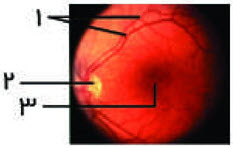

در رابطه با شکل مقابل کدام مورد صحیح است؟

در محلی که با شماره 2 نشان داده‌شده بیش‌ترین تعداد گیرنده وجود دارد.

شماره 3 از جلو با زجاجیه و از پشت با مشیمیه مجاور است.

رگ‌های خونی که در شماره 1 نشان داده‌شده از نقطه 3 منشعب شده‌است.

دندریت‌های بینایی از نقطه 2 خارج می‌شوند.

شکل مربوط به مشاهده‌ی شبکیه از درون مردمک است.

گزینه 1- شماره 2 نقطه کور است. در این محل گیرنده نوری وجود ندارد.

گزینه 2- شماره 3 محل لکه زرد را نشان می‌دهد. لکه زرد بر روی شبکیه قرار دارد و از جلو با زجاجیه و از پشت با مشیمیه مجاور است.

گزینه 3- رگ‌های خونی مشاهده‌شده در نقطه کور، از نقطه کور یعنی شماره 2 منشعب شده‌اند.

گزینه 4- آکسون های موجود در عصب بینایی (نه دندریت‌ها) از نقطه 2 خارج‌شده‌اند.